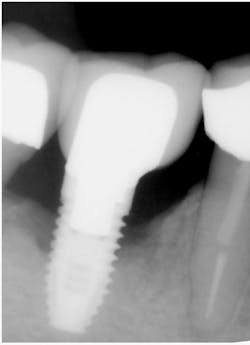

Same implant, May 2009. Solid, but ailing, showing four

threads affected. Suppurant.